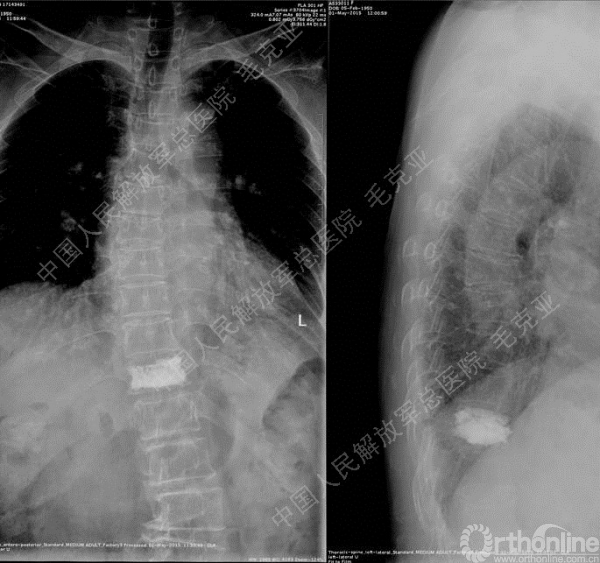

导语:随着社会老龄化的不断加速,骨质疏松性椎体压缩骨折作为一种普遍存在的老年骨科疾病已经成为现今骨科界的一个热点话题。传统的保守疗法治疗效果不佳,而现有的椎体增强技术又具有多种风险和缺陷。针对这种现状,中国人民解放军总医院毛克亚教授提供了一种新的解决方法。